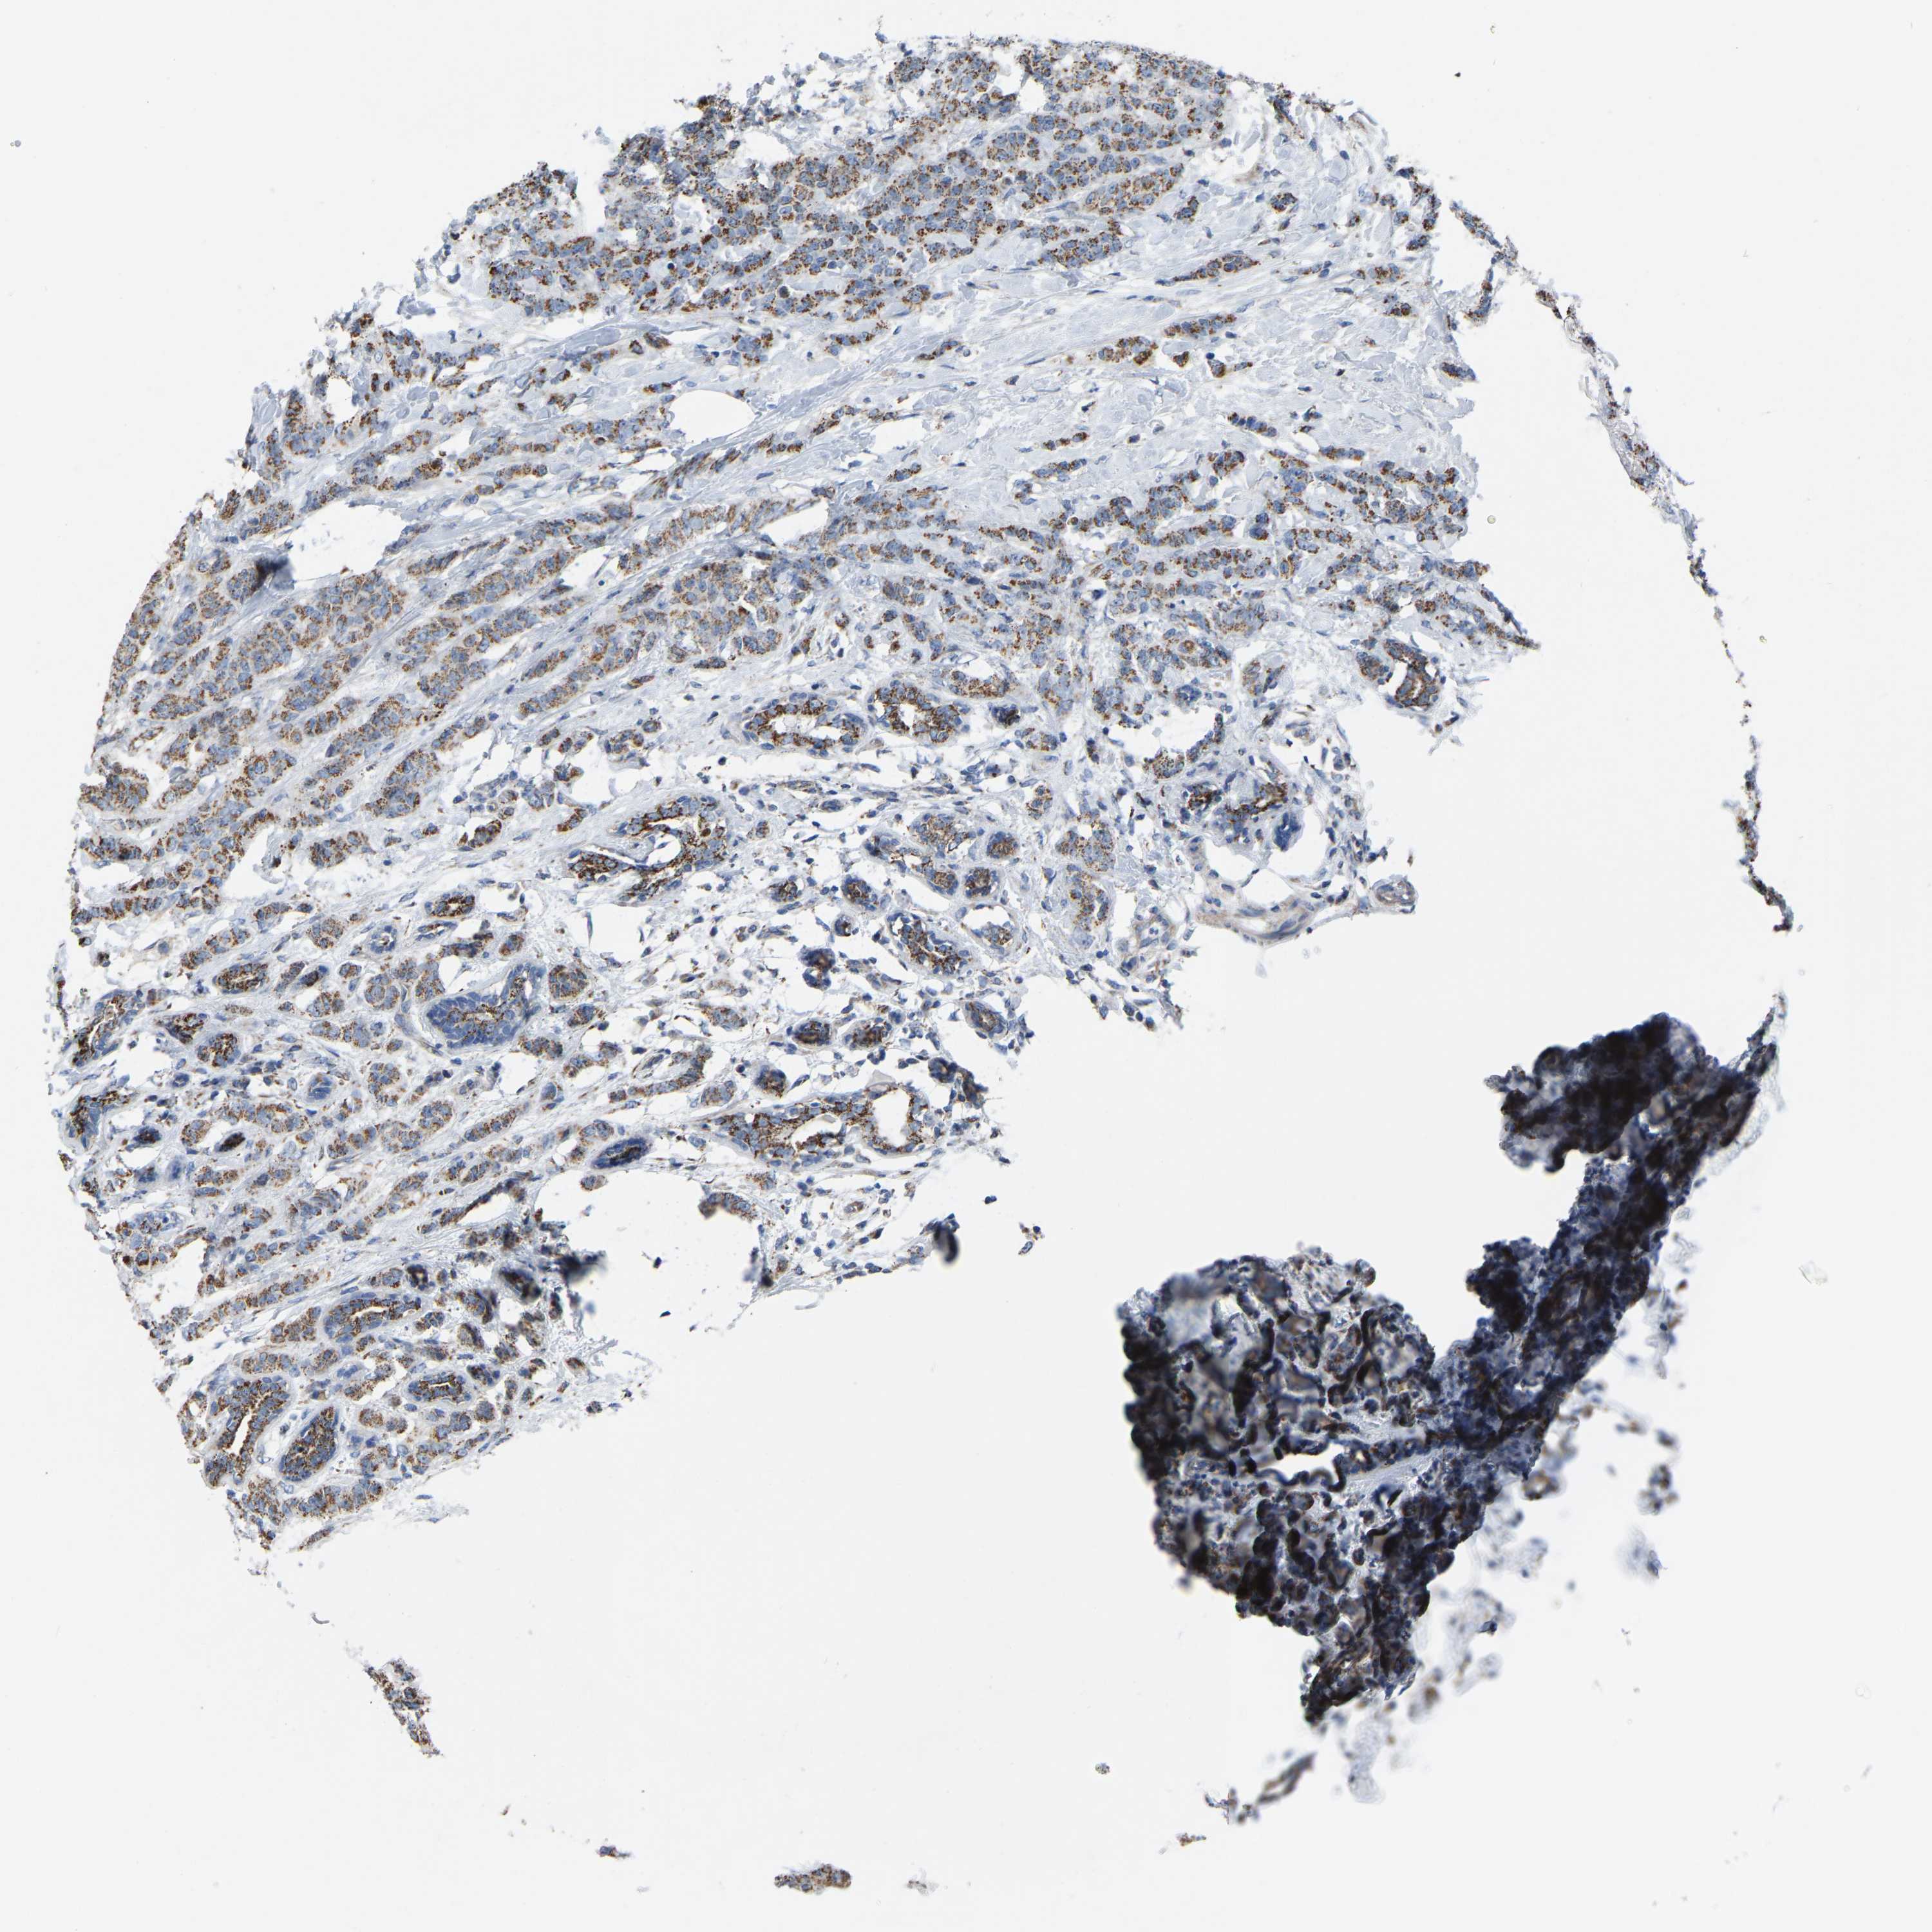

CANCER BREAST CANCER Show tissue menu

BRCA TCGA BRCA VALIDATION PROTEIN EXPRESSION